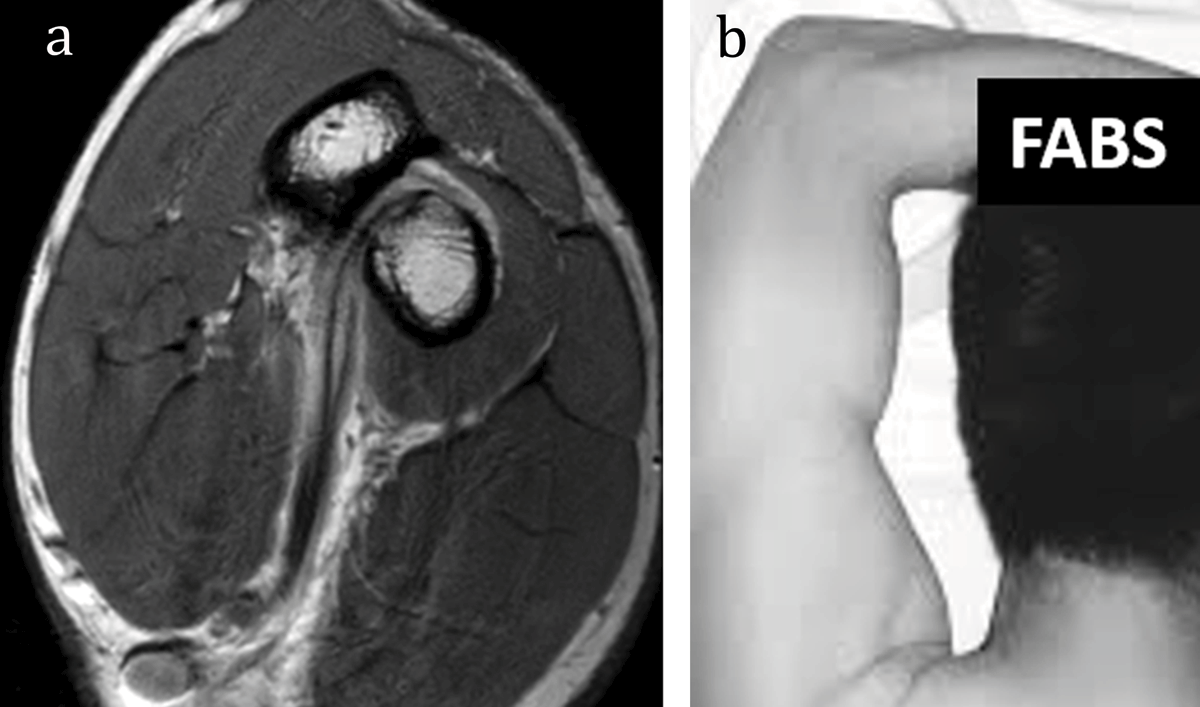

Figure 4

MR T1-weighted image (a) is obtained in FABS position with a flexed elbow, abducted shoulder, and supinated forearm as shown on the picture from Giuffre et al. (b).